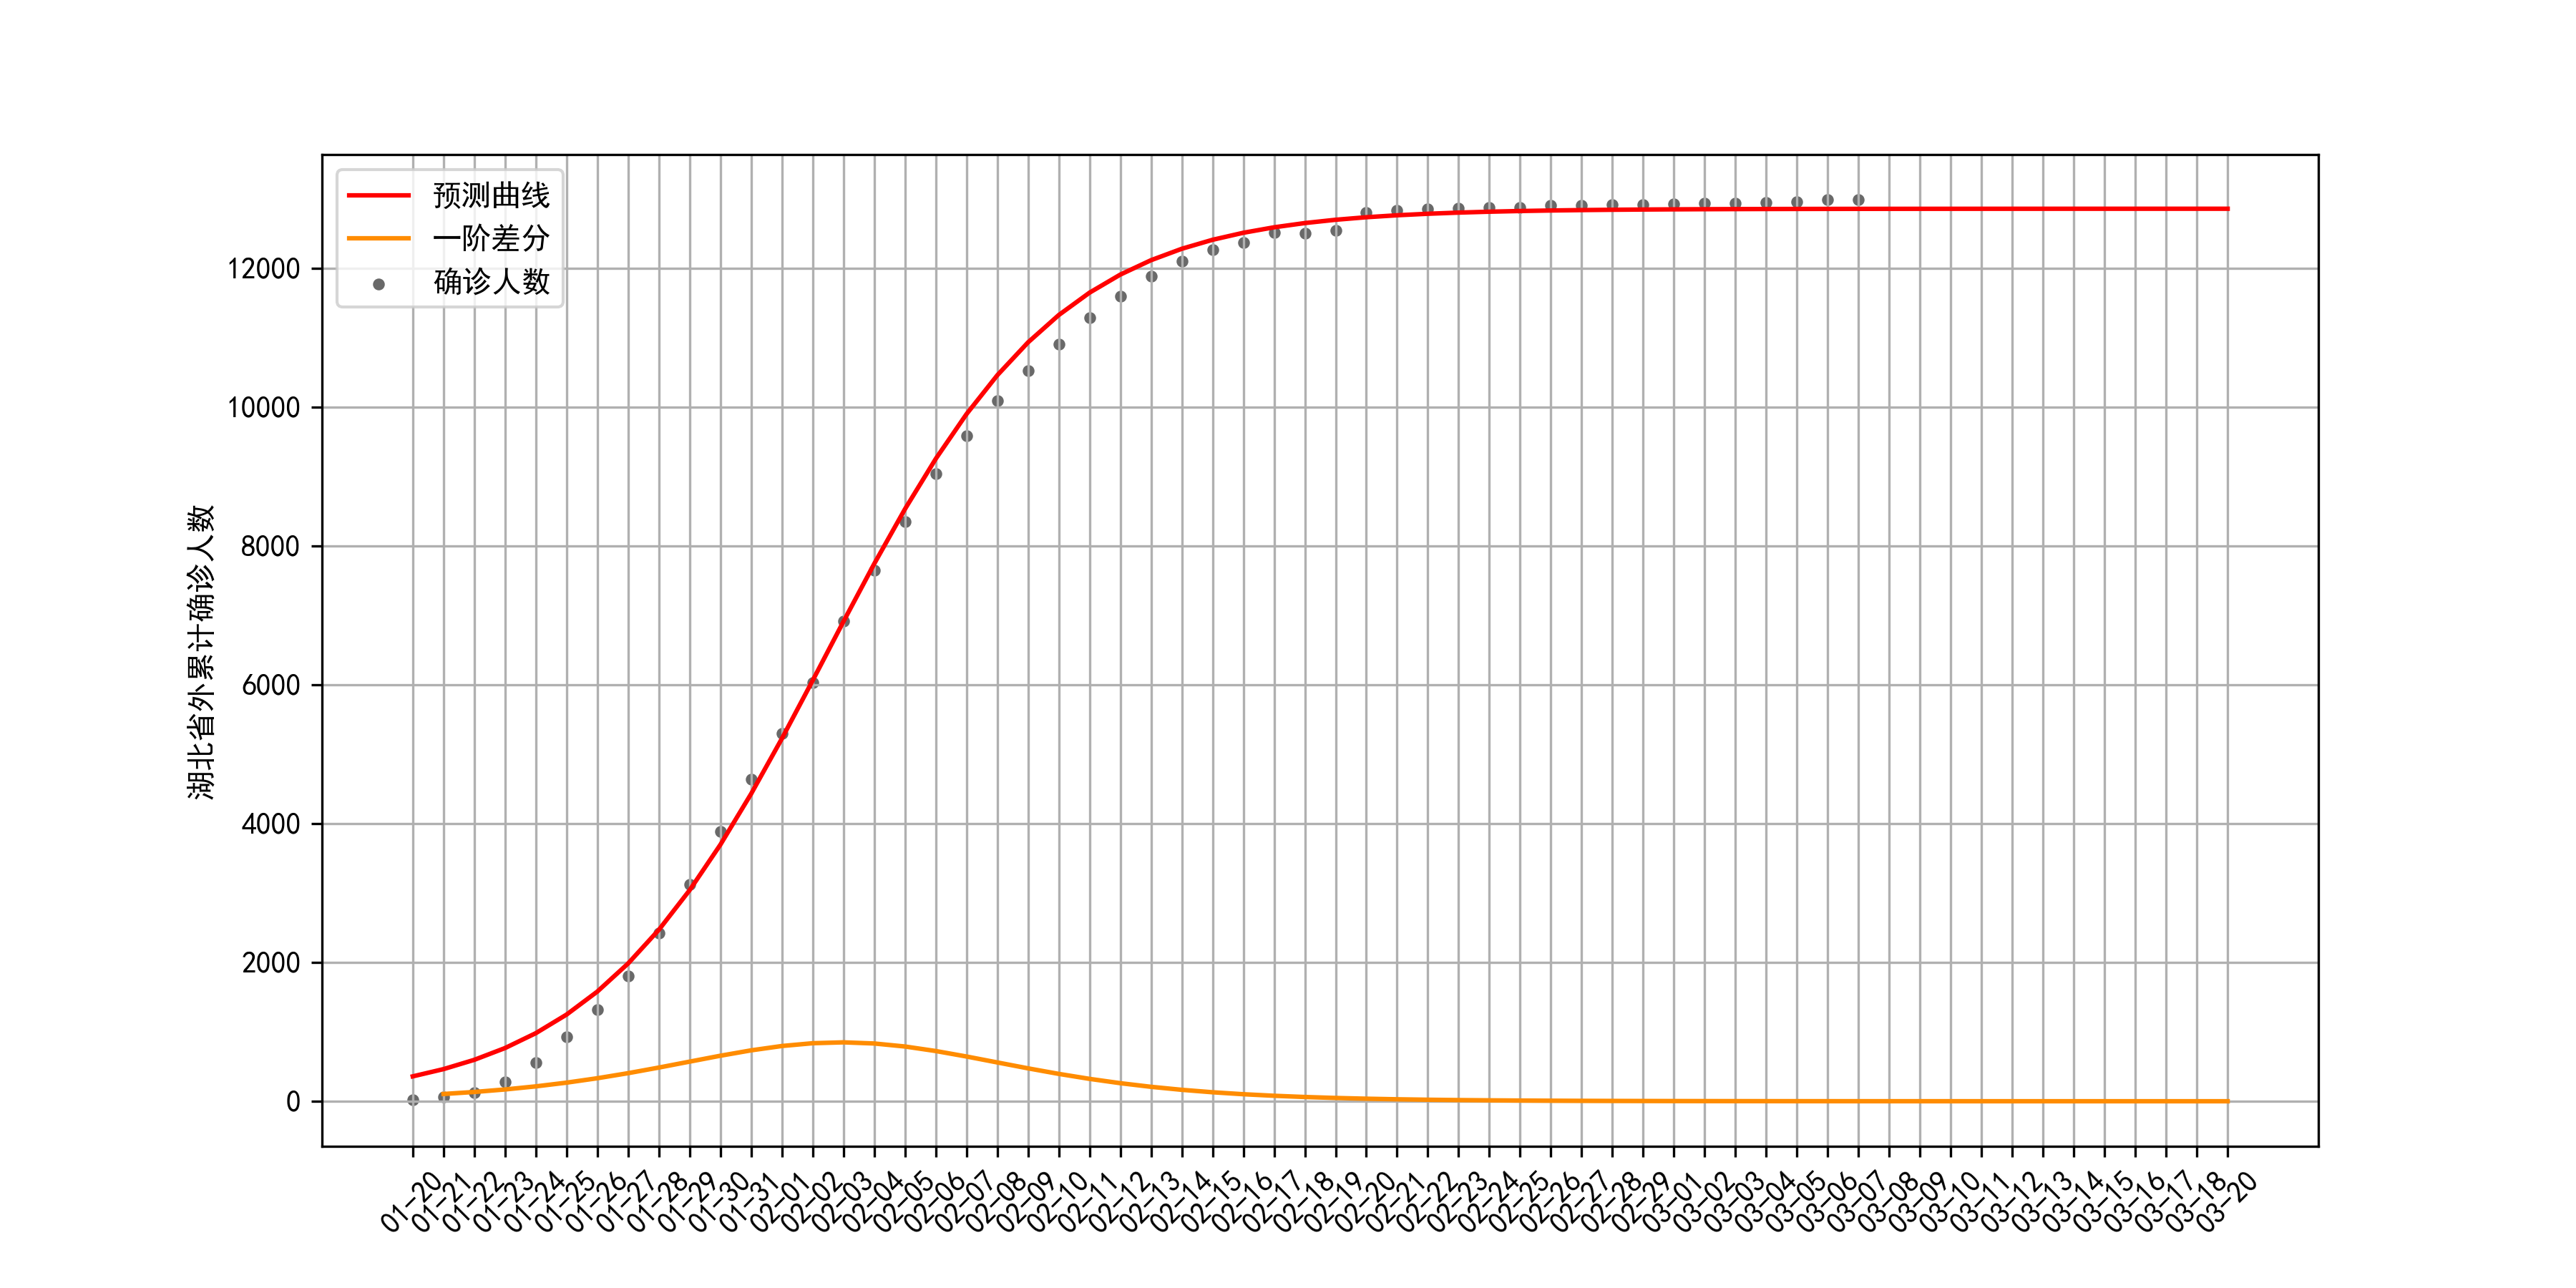

2. 用Logistic模型拟合疫情

考虑到湖北省内与湖北省外存在异质性,下面将用Logistic模型分别对湖北省与湖北省外的累计确诊人数进行拟合。首先需要获取累计确诊人数,数据来源为WindQuant提供的Wind数据接口,更多数据下载方法见获取COVID-19疫情历史数据的n种方法。

然后使用Scipy.optimezi库的curve_fit函数对Logistic曲线进行非线性最小二乘拟合。待定参数包括

2.2 湖北省外

省外疫情拟合结果:最大容量

r为0.26。疫情的拐点发生在2月3日前后,当前疫情也已经到达尾声。